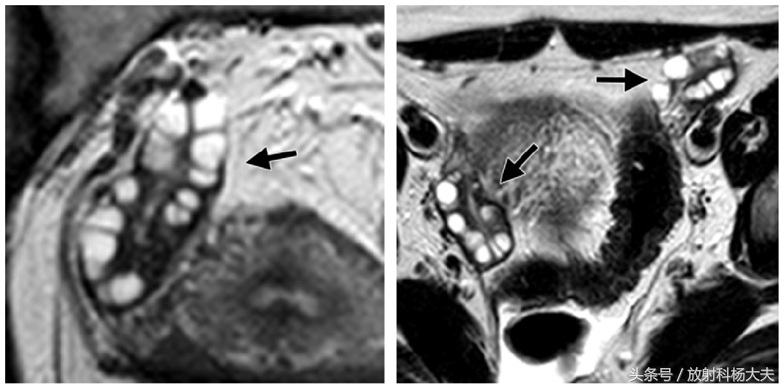

MRI属于无创检查,做过MRI的朋友都知道,患者只需要在那躺着,各项检查就这么神不知鬼不觉的完成了。而且MRI对人体没有任何电离辐射,这点尤其适合那些年轻的或者想生育的女性朋友们。MRI对软组织有极好的分辨率,可以通过多参数成像提供丰富的诊断信息,而且可以通过多角度成像选择各种剖面,获得其他成像技术所不能或难以获得角度的图像。卵巢是位于子宫两侧的一对卵圆形的生殖器官。正常卵巢信号在 T1WI上为均匀的中等或稍低信号强度,内部结构不易分辨。T2WI序列表现为多个大小不一的小圆形或小卵圆形的,均匀高信号囊性结构,囊内信号与液体一致,位于卵巢皮质内,典型呈花环样排列,以T2WI压脂序列显示最清晰。囊壁在 T1WI表现为等信号,T2WI囊壁较T1WI显示清晰,呈均匀的等低信号。在生育年龄妇女,卵巢髓质内含有大量富含血管的疏松结缔组织,T2WI上也表现为稍高信号。正常女性单侧卵巢卵泡数目6~7个,一般不超过10个,正常卵巢体积约6~7 cm3大小。在排卵期,优势卵泡的直径最大可达2 cm。多囊卵巢综合症患者的卵巢 MRI信号与正常卵巢一致,而卵巢体积较正常卵巢增大,卵泡数目较正常增多,卵泡排列无特别规律,可沿周边分布,亦可弥漫分布。与正常女性相比,多囊卵巢综合症患者双侧卵巢较正常卵巢增大2~3倍,卵巢内可见许多闭锁卵泡和处于不同发育期的卵泡,但无成熟卵泡生成及排卵迹象。